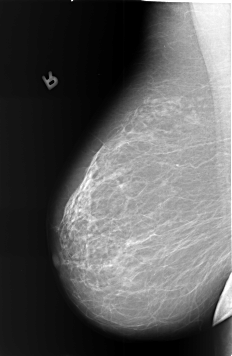

B_3401_1.RIGHT_CC

RIGHT_CC LINES 5712 PIXELS_PER_LINE 3696 BITS_PER_PIXEL 12 RESOLUTION 50 NON_OVERLAY